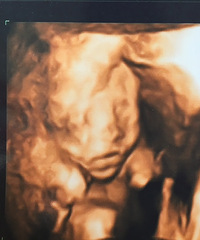

预产期:11.11(真是个特别的日子!!)建卡医院:黄岩妇幼保健院产检医院:黄岩妇幼保健院胎宝宝小名:xixi(孩他爸说以后名字上带个xi)生产医院:黄岩人民医院图片上好像是3-4个月的时候吧,现在5个半月了